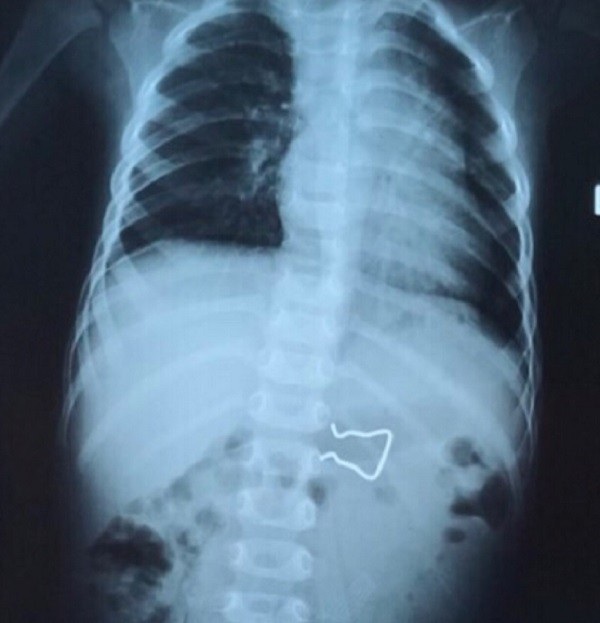

(Dân trí) - Hình ảnh X-quang phát hiện chiếc móc sắt sắc nhọn trong đường tiêu hóa của bệnh nhi, nguy cơ gây thủng ruột. Tai nạn nguy hiểm vừa xảy đến với cháu bé 18 tháng tuổi.

Bệnh nhi được chuyển đến bệnh viện địa phương rồi tiếp tục chuyển lên Bệnh viện Nhi Đồng 2. Tại đây, qua kiểm tra hình ảnh X-quang bác sĩ phát hiện, dị vật đang nằm trong đường tiêu hóa của bệnh nhi, nguy cơ gây thủng ruột nếu không được can thiệp sớm.